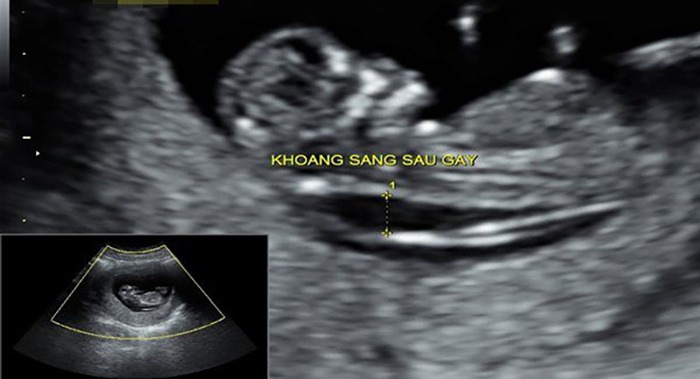

Siêu âm đo độ mờ da gáy là phương pháp kiểm tra vùng da gáy của thai nhi nhằm xác định trẻ có nguy cơ mắc các dị tật hoặc hội chứng Down hay không.

Để đo độ mờ da gáy, bác sĩ sẽ tiến hành đo theo chiều từ đỉnh đầu đến cuối xương sống của thai nhi rồi tiến đến sau gáy. Lúc này, các mẹ sẽ thấy có khoảng mờ sau gáy là một đường màu trắng xuất hiện khu vực xung quanh có màu tối hơn. Qua phần màu trắng đó bác sĩ xác định được nguy cơ mắc bệnh dị tật ở thai nhi. Ngoài ra, trên màn hình bạn còn có thể thấy các bộ phận khác như tay, chân, đầu,… của bé và cũng thấy được các điểm bất thường ở bụng hay hộp sọ của thai nhi.